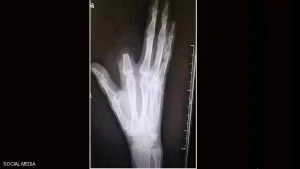

وظن الرجل أن لدغة الأفعى شديدة السمية وقد تؤدي إلى موته فورا، فسارع إلى قطع إصبعه بسكين كان بحوزته من أجل “إنقاذ حياته”، بحسب ما أوردت شبكة “فوكس نيوز”.

لكن الرجل الذي اتخذ القرار المؤلم بقطع إصبعه، لم يكن مضطرا لفعل ذلك، لأن سم هذا النوع من الأفاعي ليس قاتلا على الإطلاق، بل إنه يستخدم في تحضير علاجات للمفاصل والعظام.